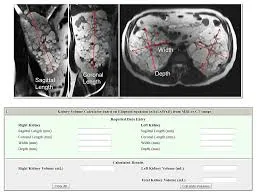

Na prática devemos solicitar um TC abdome (sem contraste) ou RM abdome par avaliar as características do rim e suas dimensões. O paciente deve ter entre 18 e 10 anos e ser classificado como típico, isto é, os cistos renais distribuídos de forma difusa e bilateral.

Devemos acessar o site da Mayo Clinic [https://www.mayo.edu/research/documents/pkd-center-adpkd-classification/doc-20094754](https://www.mayo.edu/research/documents/pkd-center-adpkd-classification/doc-20094754) .

Neste site devemos informar as dimensões renais, idade e altura do paciente, e assim teremos o resultado da classificação do paciente.

Os casos típicos podem ser classificados em 1A, 1B, 1C, 1D e 1E com base na taxa de crescimento, <1,5%, 1,5-3%, 3-4,5%, 4,5-6% e >6% ao ano, respectivamente.